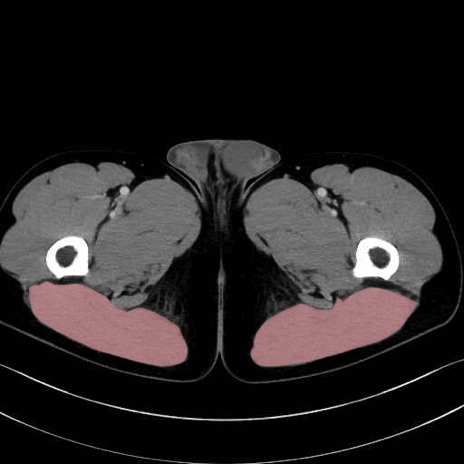

大殿筋 (Gluteus maximus)